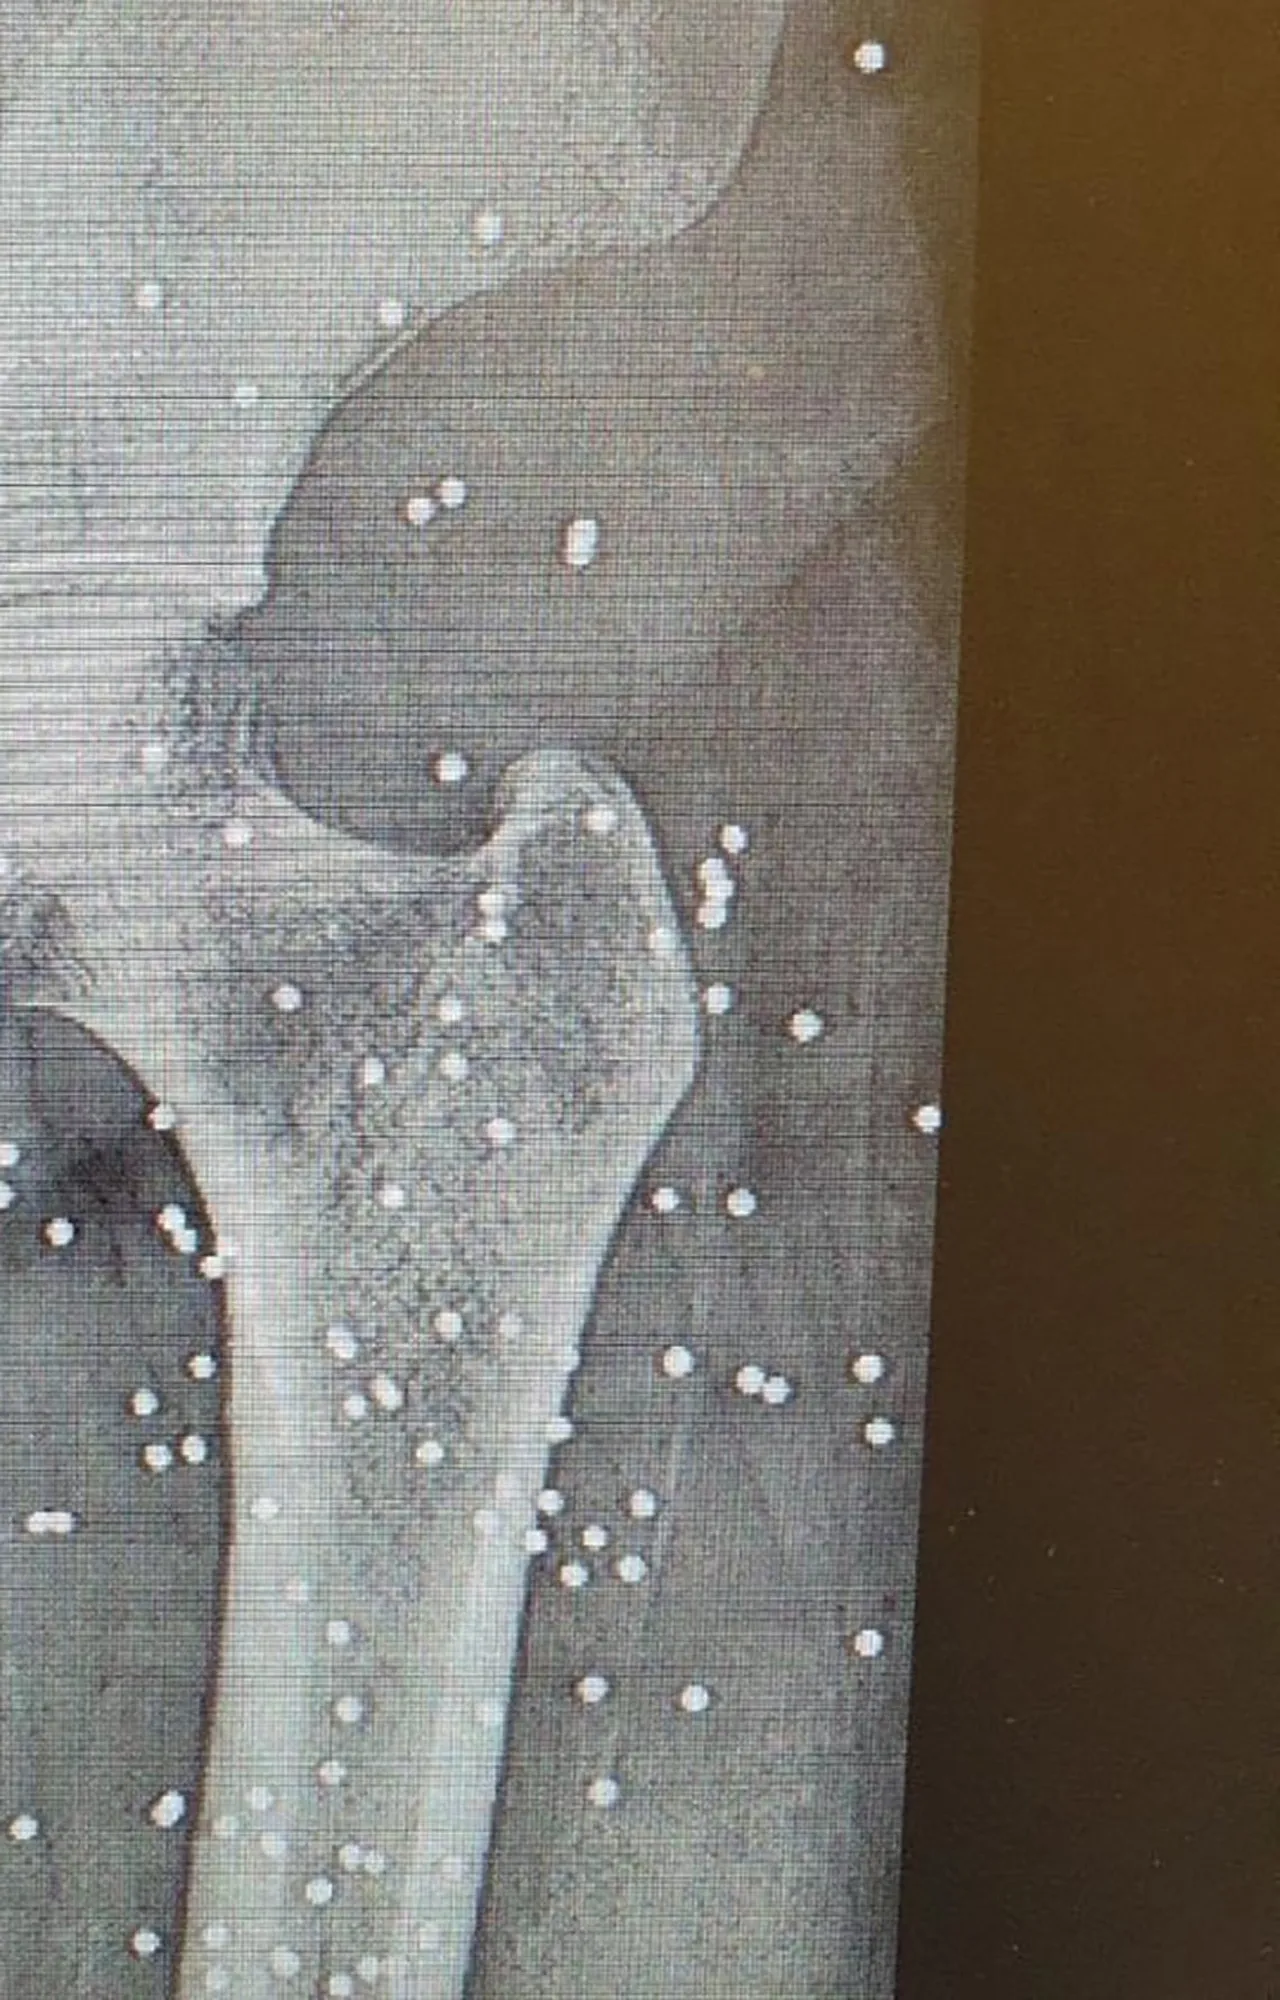

İnternet ve mobil iletişimin tamamen kesildiği 8 Ocak gecesi, hastaneler dakikalar içinde "kitlesel zayiat alanı"na dönüştü. Cerrah, başlangıçta saçma yaralarıyla gelen hastaların yerini, kısa süre sonra vücutlarının bir yanından girip diğer yanından çıkan gerçek mermilerle vurulmuş yaralıların aldığını anlattı.

Özellikle gövde yaralanmalarıyla ilgilenen ve çok sayıda mermi çıkardığını anlatan cerrah, "Uyarı atışı değildi. Bunlar onları öldürmek için kullanılan gerçek mermilerdi" ifadelerini kullandı.

Normalde bir gecede iki acil ameliyat yapılan hastanede, 9 saatte yaklaşık 18 operasyon gerçekleştirildi. Cerrah, depremlerde veya büyük kazalarda bile birkaç saatte 20-30 yaralı gördüğünü belirtirken, o gece ve sonraki günlerde gelen yaralı sayısının yüzlerle ifade edildiğini söyledi.